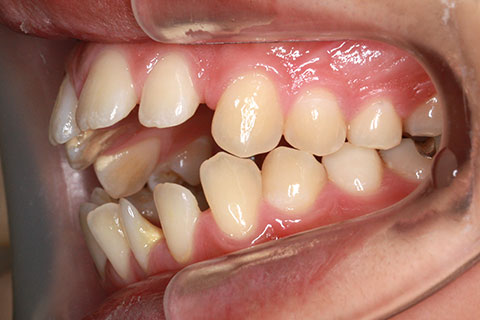

治療中

治療後